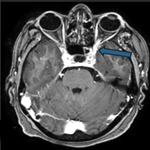

Tolosa-hunt syndrome: unraveling painful ophthalmoplegia through imaging

Devyansh Nimodia, Pratapsingh Hanuman Parihar

PAMJ-CM. 2025; 19: 13. Published 03 November 2025